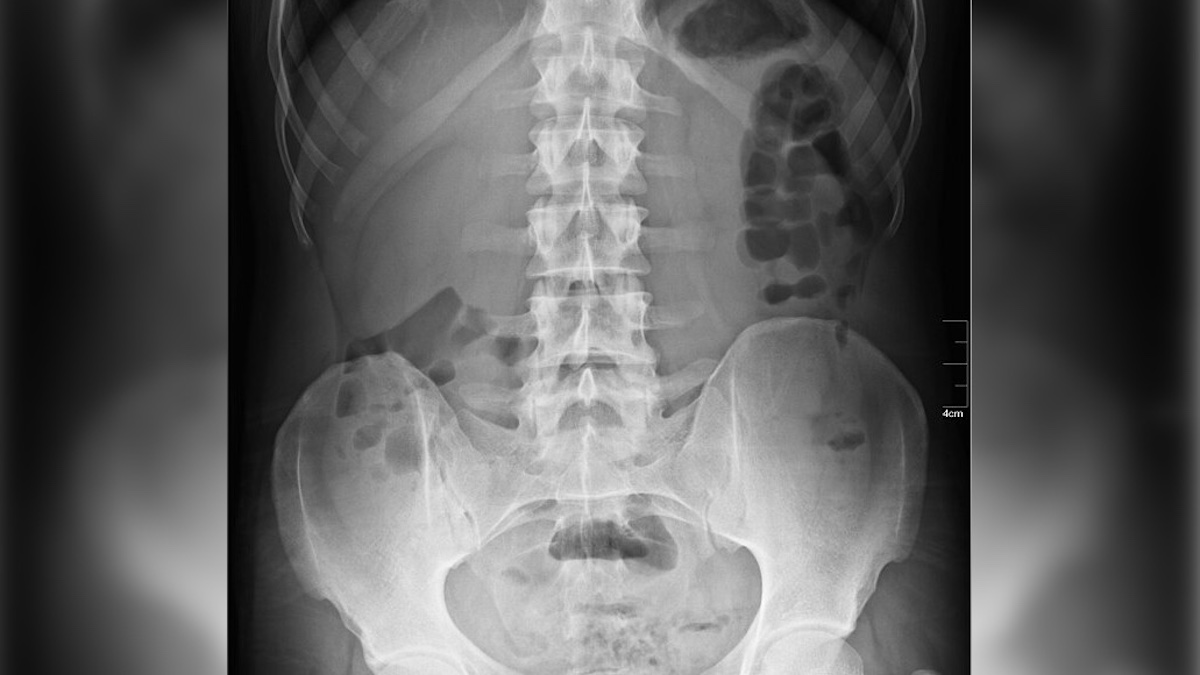

However, an X-ray revealed something astonishing that quickly gained international medical attention: a calcified fetus, a rare condition known as a lithopedion or “stone baby,” which had been in her body for approximately four decades.

The elderly patient had experienced a rare abdominal pregnancy many years earlier. This occurs when a fertilized egg implants outside the uterus, typically in the abdominal cavity. The fetus had developed for several months before dying. Crucially, because the body could not naturally expel the deceased tissue, it initiated a protective defense mechanism. To shield the woman from infection, her immune system slowly encased the fetus in layers of calcium, effectively turning it into a protective, stone-like mass.

This calcified mass reportedly weighed about four pounds. The condition often goes undetected for years or even decades, as many women experience minimal to no symptoms. Diagnosis typically occurs only when imaging is performed for a different medical issue. In this Colombian case, doctors theorized that the woman’s pain stemmed from the lithopedion pressing on her internal organs as she aged.